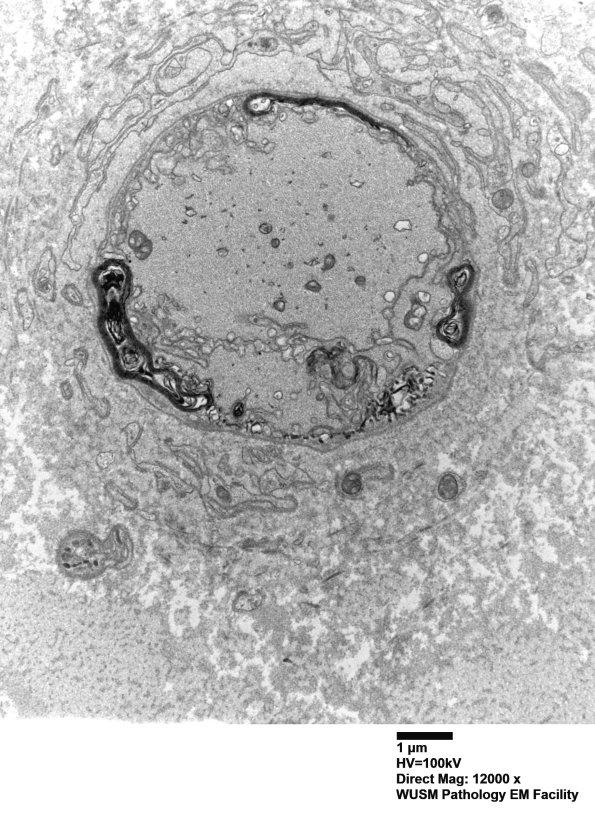

16I1,2 In these axons the intra-axonal process appears similar; however, what are the proliferative membranes exterior to the axon borders? (electron micrographs)